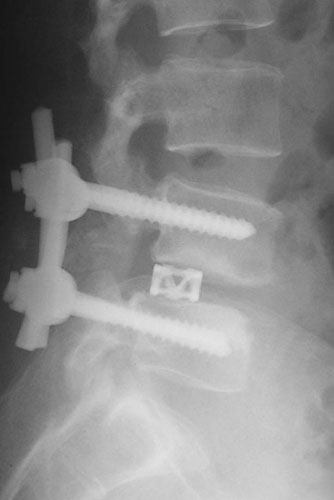

Spondylolisthesis malformations

Spondylolisthesis implies slippage of one lumbar vertebra over the next one, causing pain and nerve compression. Patient can also have difficulty in walking and numbness of the legs. Usually these patients need evaluation lumbar spine by MRI and CT scan, followed by spinal instrumentation and fusion.